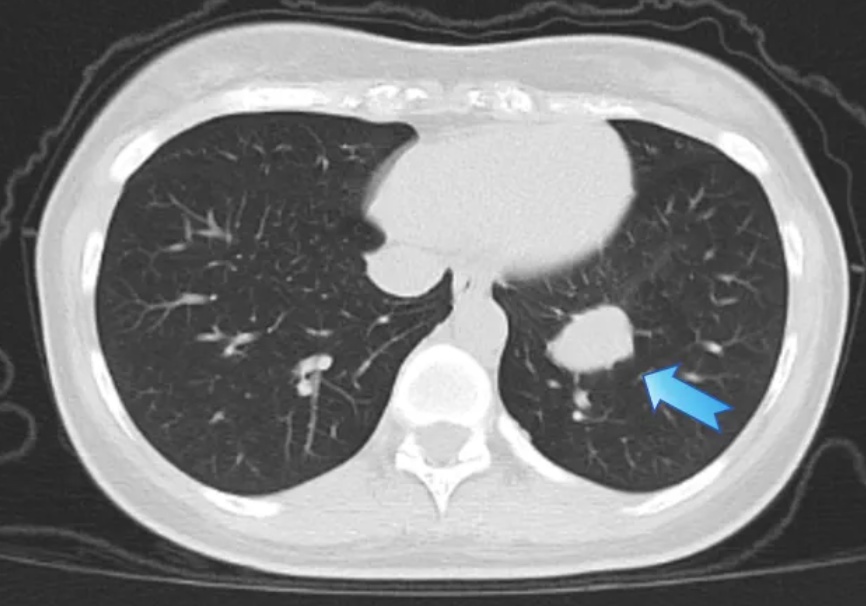

以为是个肺结节,没想到是个“定时炸弹”

今年8月中旬,28岁的王女士(化名)在家中突然咳出鲜血,起初觉得只是咽喉炎或空气干燥引起的。没想到连着咳血,她赶紧前往当地医院就诊,胸部CT提示:左肺下叶约1.6 cm结节影,医生初步考虑为“结核球”。